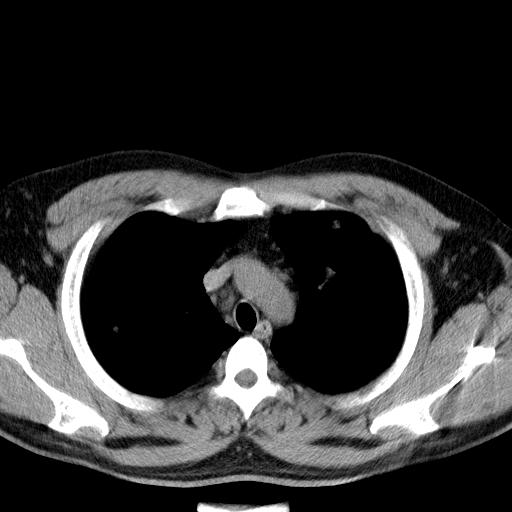

患者男性 35 主因发热咳嗽四天,血象不高,心肺听诊未见异常,无其它病史及传染病接触史。

两肺散在大小不等小结节影,下野较多,纵隔淋巴结增大。考虑:1、慢性血播性肺结核;2、霉菌病?3转移瘤待排。

两肺多发结节,部分病灶边缘不清,且示毛玻璃影。分布特点为沿血管支气管分布。

结合临床考虑;1,炎性肉芽肿性病变;霉菌?过敏性肺炎?2,韦格氏肉芽肿。3,转移瘤。